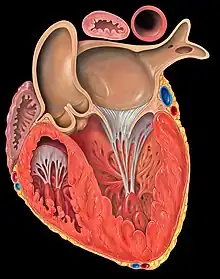

La contraction ventriculaire suit la contraction atriale, et est plus puissante et plus longue que celle-ci. Lorsque l'espèce possède deux ventricules, ils sont séparées par une paroi musculaire épaisse appelé le septum interventriculaire. Le sang est expulsé vers l'artère pulmonaire par le ventricule droit, et vers l'aorte par le ventricule gauche. Les ventricules sont séparés des atria (du terme désuet « oreillettes ») par les valvules mitrale et tricuspide, et des artères cardiaques par les valves aortique et pulmonaire.

Le ventricule gauche reçoit le sang oxygéné par l'atrium gauche et le propulse dans le corps par l'aorte.

Le ventricule droit reçoit le sang veineux par l'atrium droit et le propulse vers les poumons par l'artère pulmonaire.